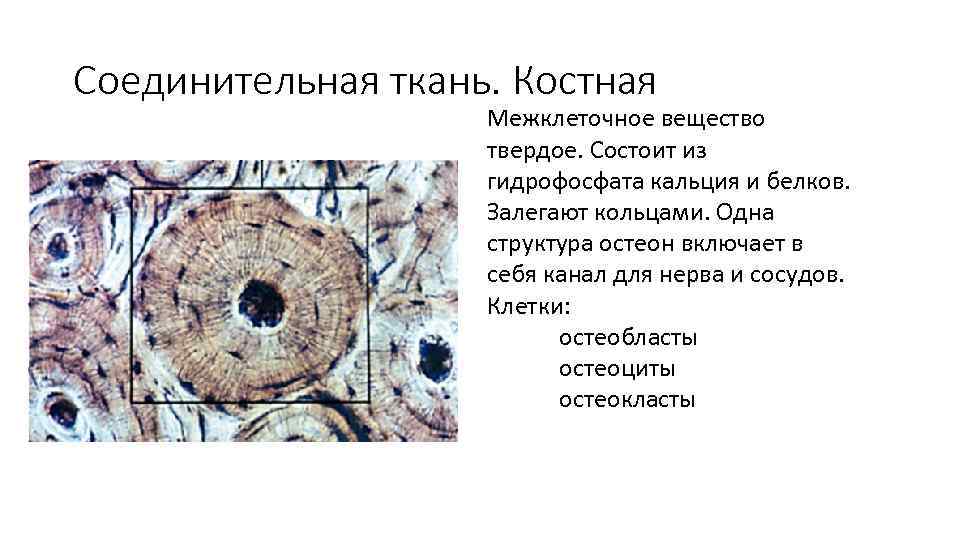

Структура грубоволокнистой костной ткани: наглядные примеры

Раздел: Дом и быт